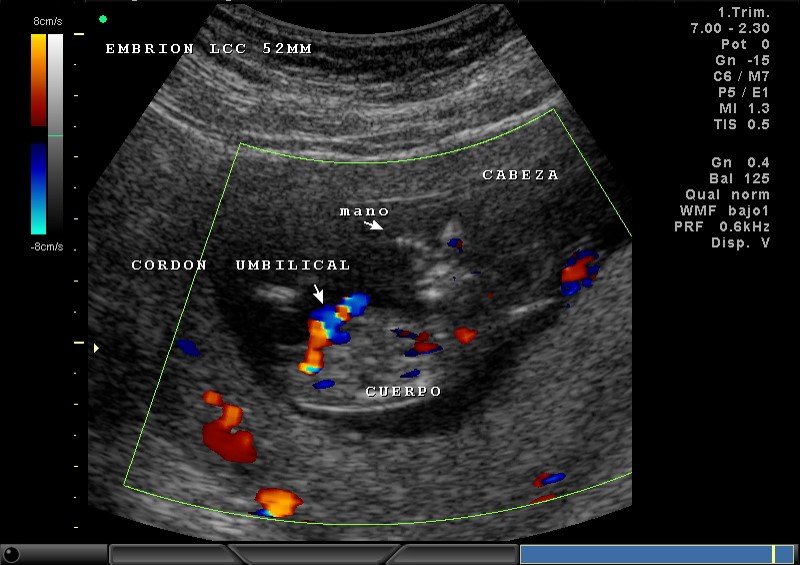

2D Y COLOR PLACENTA, ABDOMEN, CABEZA, MANO 11.5 SEMANAS